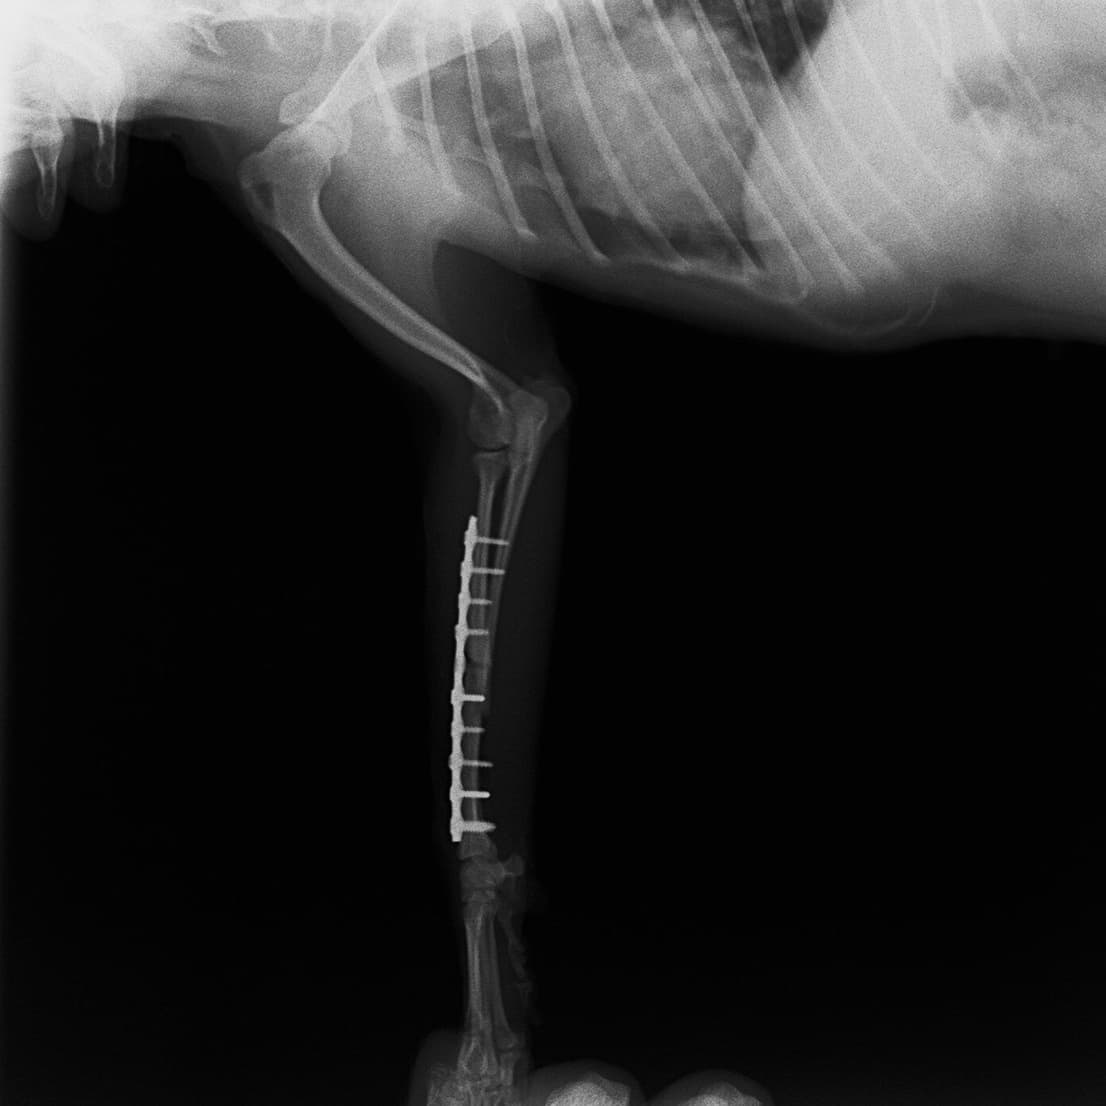

柴犬:9歳、避妊雌

交通事故直後、胸腰部に激しい疼痛、両後肢に完全麻痺を認め、シェフシェリントン徴候を呈していました。レントゲン検査において、第11-12胸椎間の脱臼が認められました。

脊髄の減圧、脊柱管の再構築・安定化を目的に、片側椎弓切除術およびMatrixMANDIBLE Plateによる椎体固定を実施しました。

隣接椎体を架橋するようにプレートを設置しました。

術後レントゲン写真